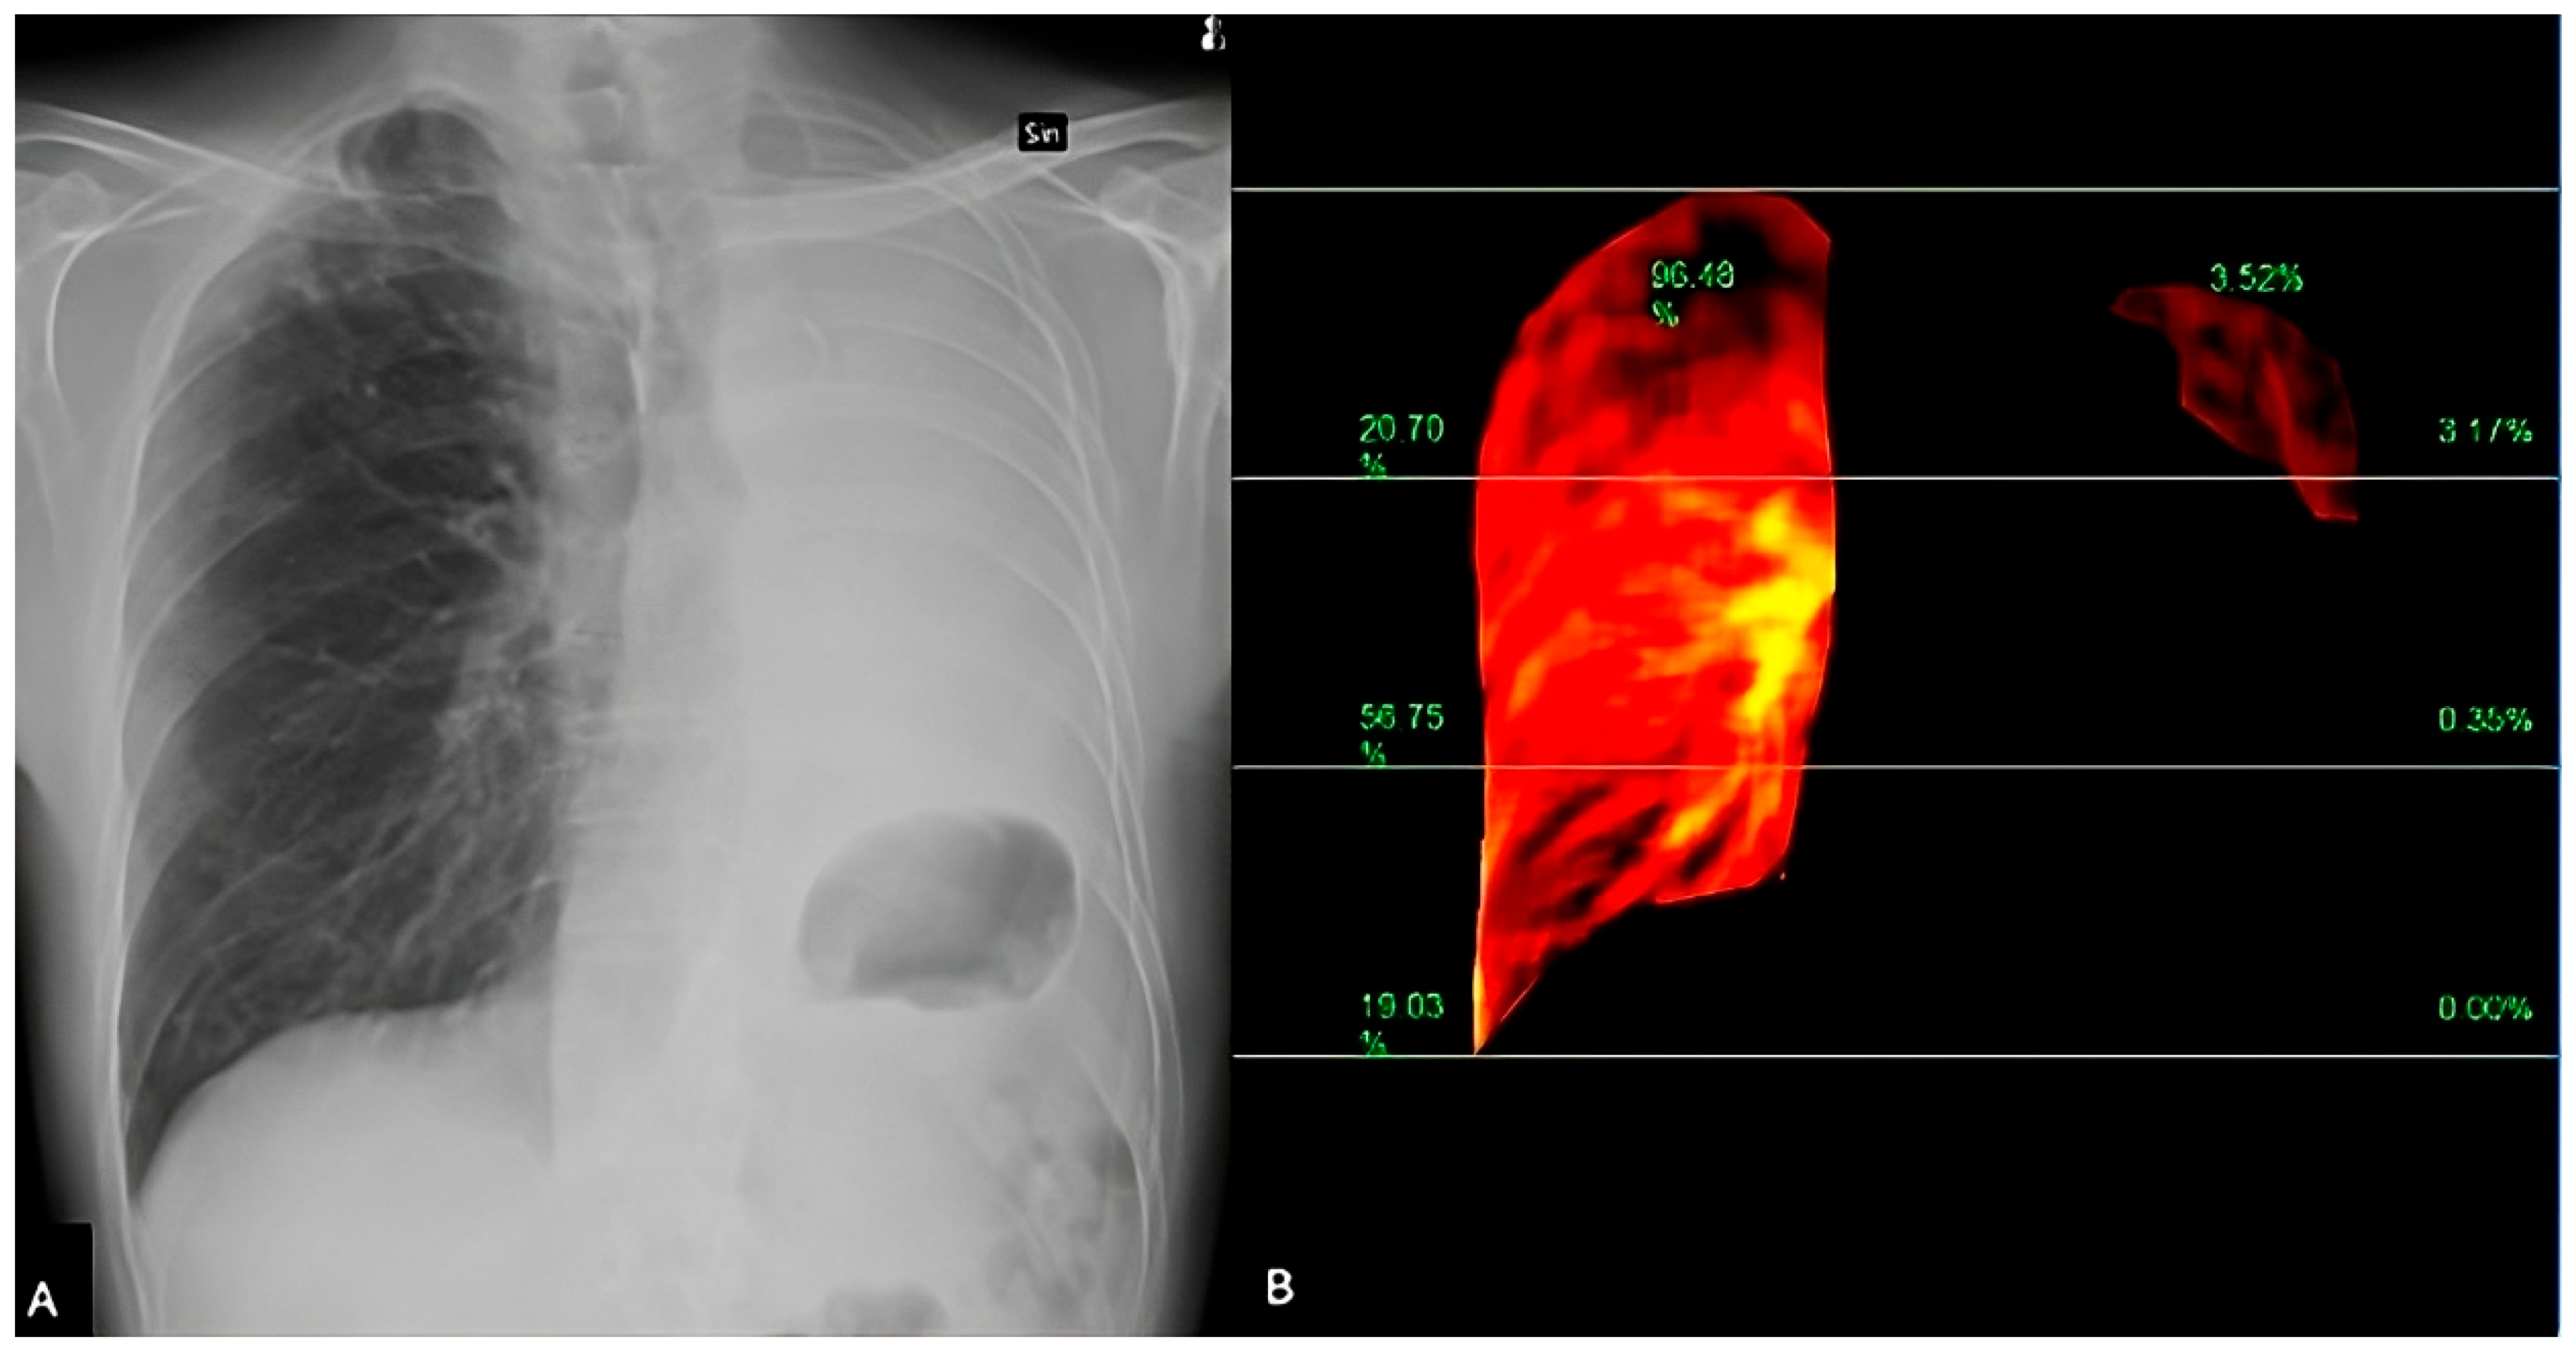

3.4. Dynamic Digital Radiography

3.4.1. Principles of Dynamic Digital Radiography

3.4.2. Accuracy of Dynamic Digital Radiography